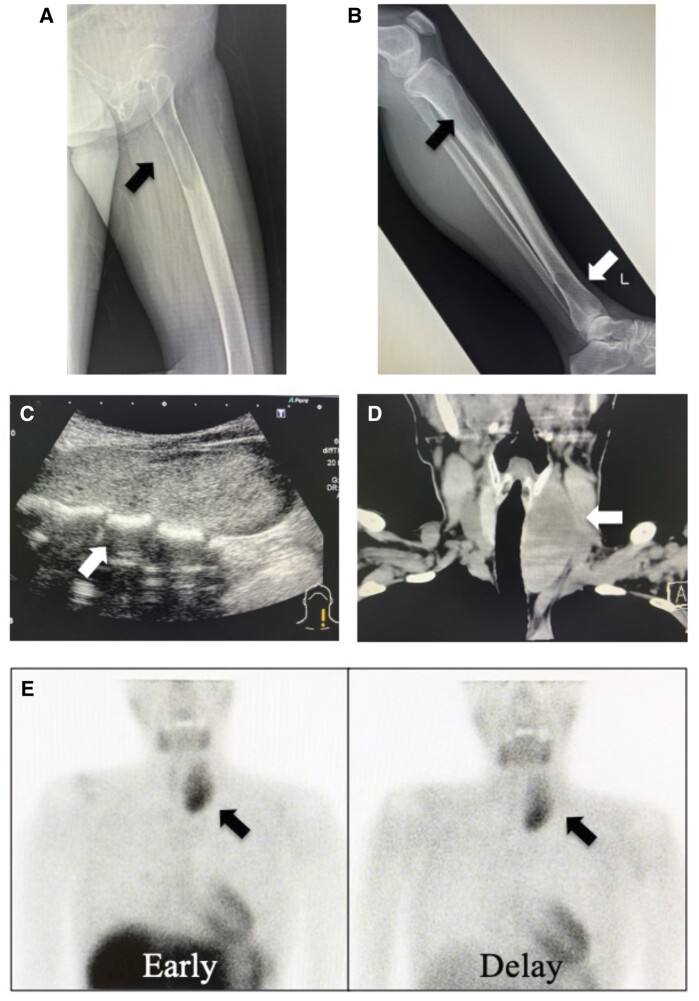

We present two rare cases of parathyroid carcinomas associated with multiple brown tumours. Plain radiographs, computed tomography, and neck ultrasonography revealed the presence of bone and parathyroid tumours. Despite the use of 99m Tc-methoxy isobutyl isonitrile (99mTc-MIBI) or 18F-fluorodeoxyglucose-positron emission tomography (18F-FDG PET)/CT, it was difficult to differentiate bone metastases from brown tumours. Parathyroid carcinoma was confirmed by histopathological examination following parathyroidectomy, resulting in spontaneous bone lesion improvement. In patients with parathyroid carcinoma presenting with bone lesions suggestive of metastasis, understanding the potential for brown tumour accumulation through 99mTc-MIBI or 18F-FDG PET/CT is pivotal. With this understanding, it is possible to diagnose brown tumours with parathyroidectomy and follow up for improvement of bone lesion and avoid invasive biopsy or surgery.